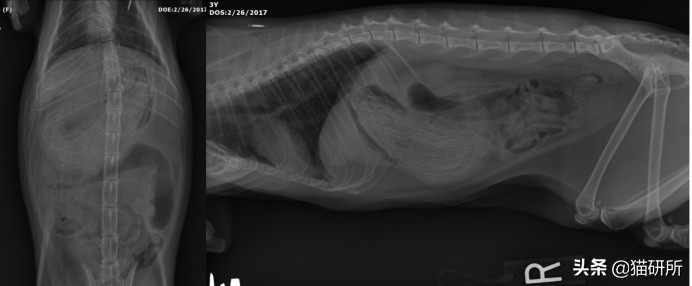

本文开头引起大家热烈讨论的那张X线片并不是什么芒果榴莲大蒜,而是尿石症家族成员之一——膀胱结石。尿石症可以发生于泌尿系统(肾、输尿管、膀胱、尿道)的任何部位。

图自:猫研所动物医院和纳吉亚动物医院